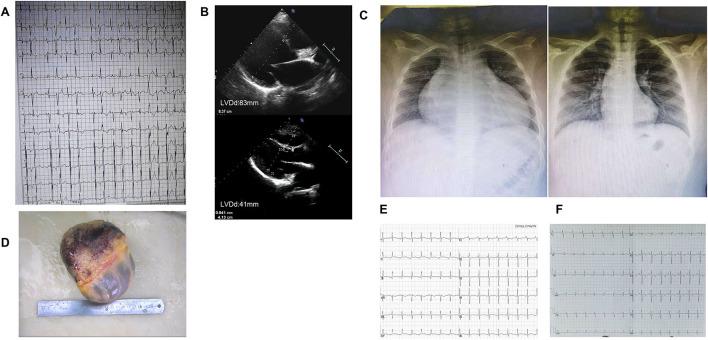

We report a 3-generation family with c.611 C>A rare variant, whose clinical characteristics are dilated cardiomyopathy (DCM) combined with multifocal ectopic Purkinje-related premature contractions (MEPPC). We tried to explain why the same variant carriers had different phenotypes.

Information was collected from 15 people in this family, 8 of whom had genetic testing. The variant was present in all patients of this family, whose clinical features showed DCM combined with MEPPC. The proband's children developed DCM and MEPPC in their childhood. They both carried a p.A204E mutation from their mother and a mutation p.D372N from their father. The son did heart transplant and his heart was both dilated and thickened. The pathology confirmed the presence of glycogen accumulation in the myocardium, which were consistent with the diagnosis of syndrome.

我们报告一个携带c.611 C>A罕见变异的三代家系,其临床特征为扩张型心肌病(DCM)合并多灶性浦肯野相关室性早搏(MEPPC)。我们试图解释为何相同变异携带者具有不同表型。

从该家系15人中收集了信息,其中8人进行了基因检测。该变异存在于该家系所有患者中,其临床特征表现为DCM合并MEPPC。先证者的孩子在童年时患DCM和MEPPC。他们均从母亲那里遗传了p.A204E突变,从父亲那里遗传了p.D372N突变。儿子接受了心脏移植,其心脏既有扩张又有增厚。病理检查证实心肌中存在糖原蓄积,这与综合征的诊断相符。